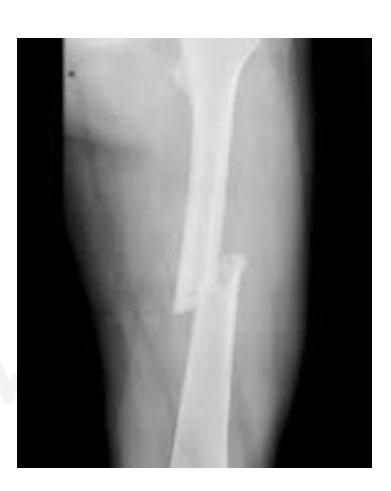

Tibia and Fibula Fracture

Diagnosis: Segmental and comminuted fracture of tibia and fibula